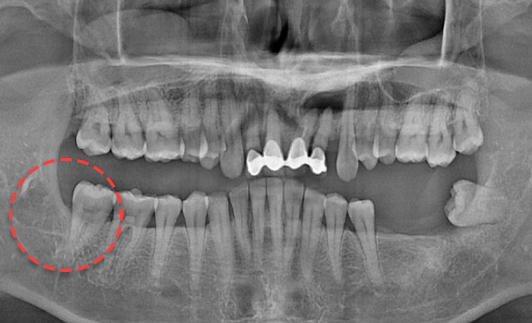

• BEFORE

양쪽 하악 매복 사랑니 발치 Before X-Ray

치료시작일

2019.11.05

AFTER

양쪽 하악 매복 사랑니 발치 After X-Ray

치료종료일

2020.12.24

양쪽 하악 매복 사랑니 발치